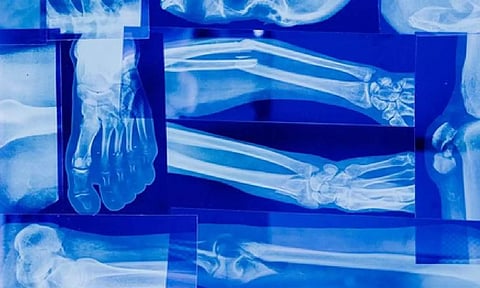

NEW DELHI: Strong bones form the foundation of a healthy and active lifestyle, supporting our body's structure and protecting vital organs. However, as we age, our bones naturally undergo a gradual loss of density, making them more susceptible to fractures and breaks.

Bone weakness, or osteoporosis, is a common condition characterised by decreased bone mass and compromised structural integrity. In this article, we will explore the signs that indicate your bones may be weak, empowering you to take proactive steps to maintain bone health and prevent potential complications.

One of the most apparent signs of weak bones is experiencing frequent fractures or breaks, often from minor injuries or falls. Individuals with weakened bones may find that they suffer fractures more easily and that these injuries may take longer to heal than expected. If you notice an increased vulnerability to fractures, it's essential to seek a medical evaluation to determine the underlying cause.